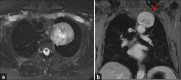

Schwannomas are benign soft-tissue tumors that arise from peripheral nerve sheaths throughout the body and are commonly encountered in patients with neurofibromatosis Type 2. The vast majority of schwannomas are benign, with rare cases of malignant transformation reported. In this pictorial review, we discuss the magnetic resonance imaging (MRI) appearance of schwannomas by demonstrating a collection of tumors from different parts of the body that exhibit similar MRI characteristics. We review strategies to distinguish schwannomas from malignant soft-tissue tumors while exploring the anatomic and histologic origins of these tumors to discuss how this correlates with their imaging findings. Familiarity with the MRI appearance of schwannomas can help aid in the differential diagnosis of soft-tissue masses, especially in unexpected locations.